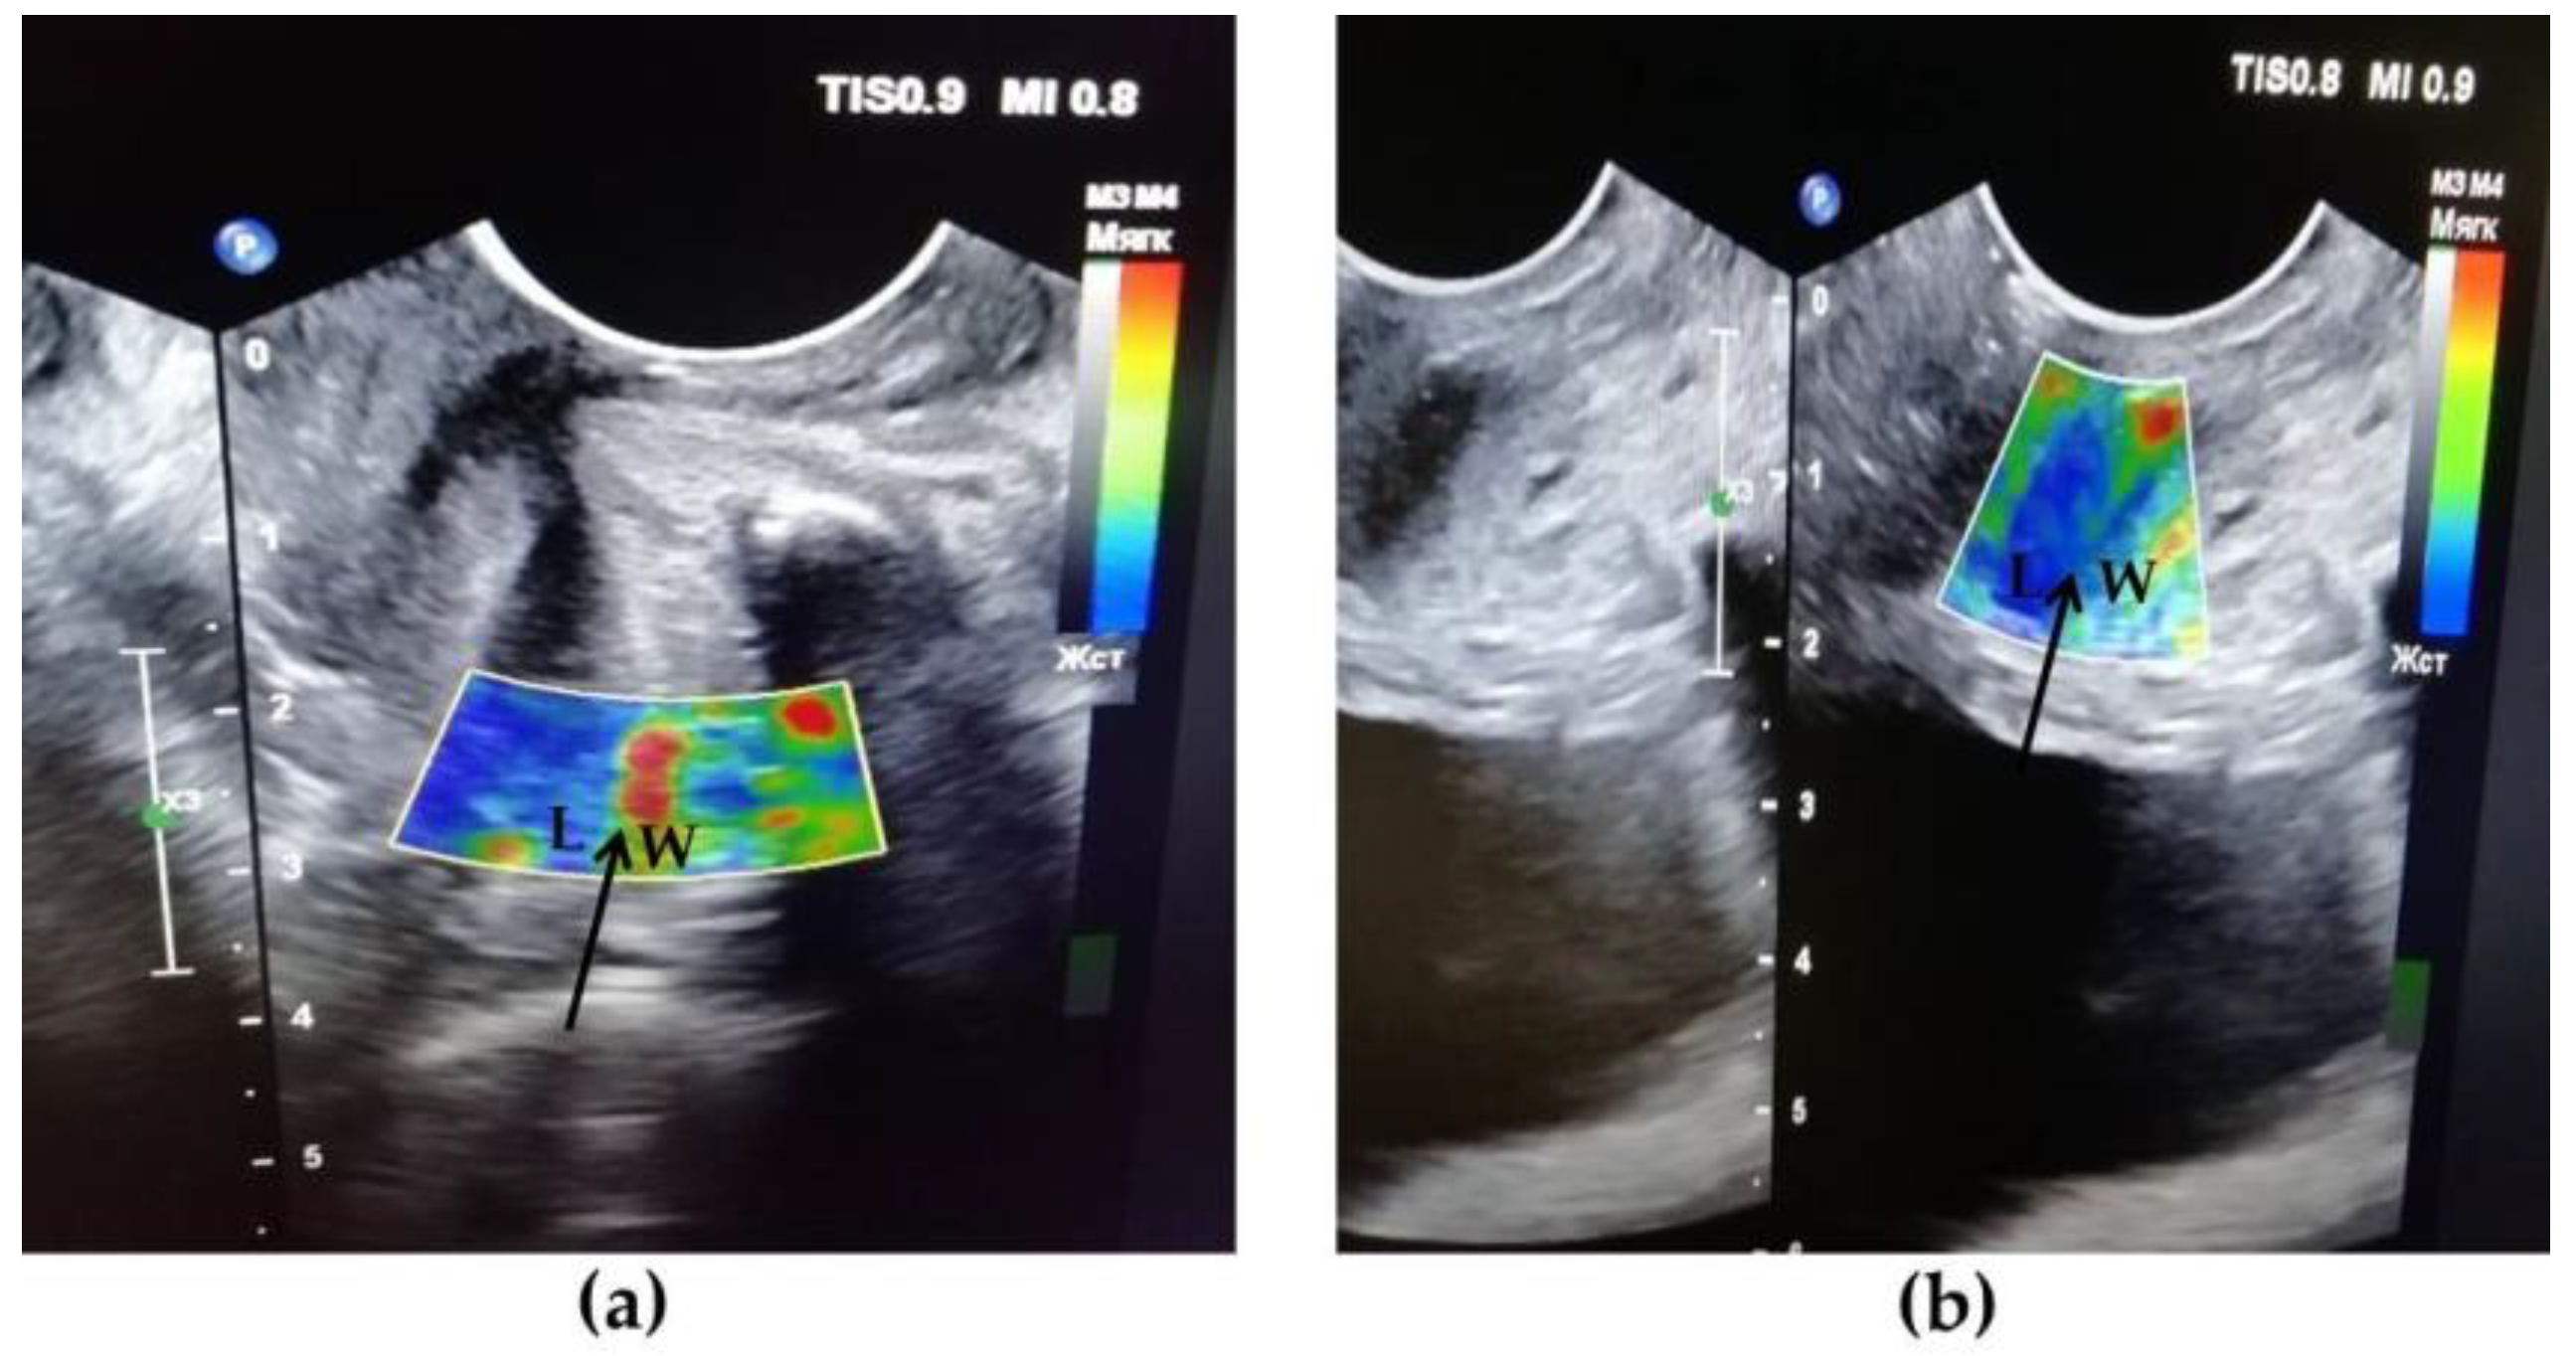

3.4. Results of TVUS Research

| 5. Transvaginal US/compression US | assessment of the size, shape, structure of the urethra and bladder neck/mapping of the urethral wall and surrounding tissues stiffness | 24 | 6 |